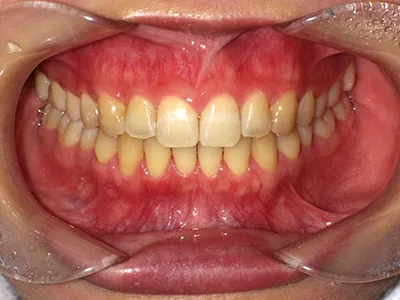

症例3

before

after

| 主訴 | 歯並びきれいにしたい、噛み合わせ良くしたい |

|---|---|

| 治療内容 | マウスピース矯正 |

| 治療期間 | 1年 |

| 費用 | 770,000円(税込) |

| リスク・副作用 | 矯正期間中、歯の移動に伴い、痛み、染みる症状が出ることがあります |